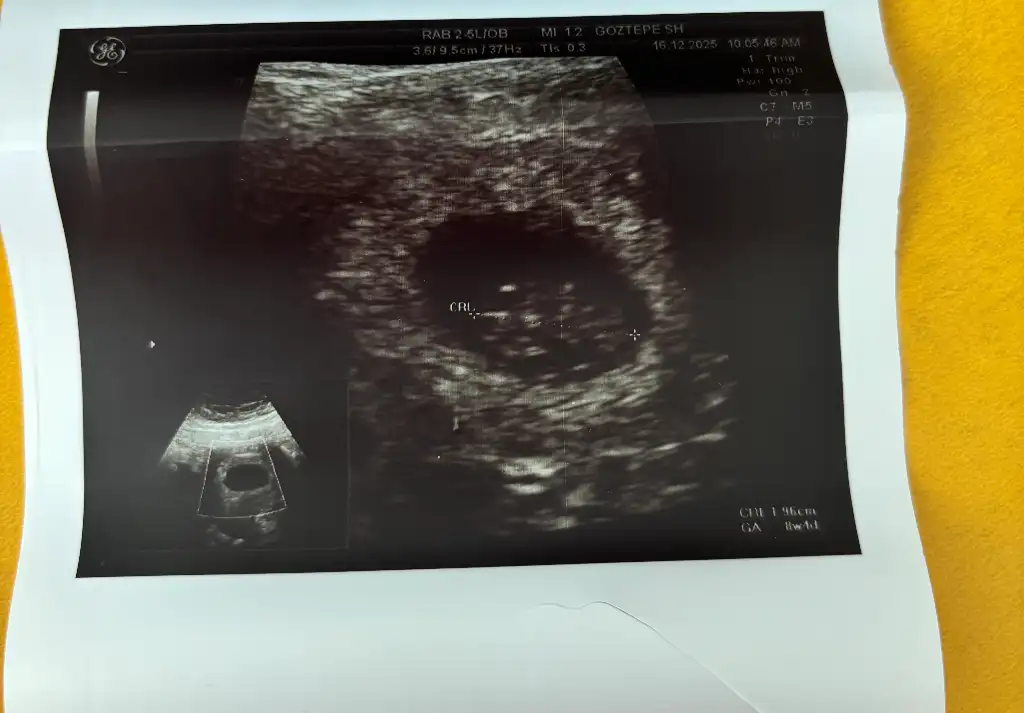

Kızlar tekrar paylaşmak istedim içiniz rahat etsin diye ben 5+1 de keseyi gördüm 4+5 uyumluydu daha sonra 6+1 de gittim 5+6 uyumluydu hem karından hem vajinal bakıldı ikisini de ekledim oluşum var ama bebek yoktu henüz 7+1 de gittim 6+6 çıktı bebek ve kalp atısı duyuldu görüldü korkmayın 7. Haftadan sonra görülüyor genelde zaten cok normal her bebeğin gelişimi farklı her gebelikte diğerlerinden farklı oğlum da da 6+5 de bebeği görmüştüm ama kalp dinletmemişti 7+5 de gittiğimde dinletmişti ve o haftalar da hep 4 gün geri çıkıyordu yani bunlar cok normal lütfen artık sitres yapmayın

Eklentiler

• IMG_4154.webp

IMG_4154.webp

12,6 KB · Görüntüleme: 11

• IMG_4153.webp

IMG_4153.webp

26,4 KB · Görüntüleme: 11

Ayna efekti var mı bilmiyorum rami teorisine göre ekranın sağı kız, solu erkekmiş. Yerleşime göre :D nub teorisi için de belirgin değil fotoğraf:D

Evt ya cihaz pek iyi değil bebişte minik daha. Solda gibi sanki şu uzaktan görünende anlayamadım tam ortada mı yoksa 😂 off 😂

Soldaymış seninki, chatgpt öyle dedi sorsana onaa :) ama daha kaliteli fotoğraf al bi dahakine. Özel takipli misin